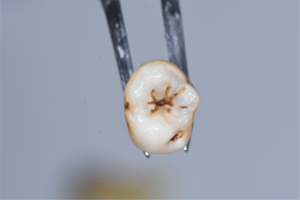

写真で見るとわかるかもしれませんが、初期の虫歯は着色して茶色くなっています。

この場合、茶色い部分を探針で探ってみると硬い場合がほとんどで虫歯の柔らかさを感じることがありません。

初期虫歯は、ほとんどの場合が石灰化して白くなった部分に着色している状態が多いですね。

そのため、患者さんから見えるような部分ですと多くの患者さんがこれは虫歯なのではないか?と聞かれることがあり、レントゲンを撮ってみると虫歯のような影もなく、探針で触ってみても硬い場合がほとんどです。

初期虫歯の状態の抜歯後の歯の写真

初期虫歯の診断は、非常に難しいです。歯科医師によって虫歯の診断は様々ですし、基準も違います。患者さんによっては、初期虫歯を削られたとおっしゃる方がいますが、お口の中を見てみると汚れだらけで、初期虫歯でも放っておいたら虫歯が進行してまうようなケースが多いです。